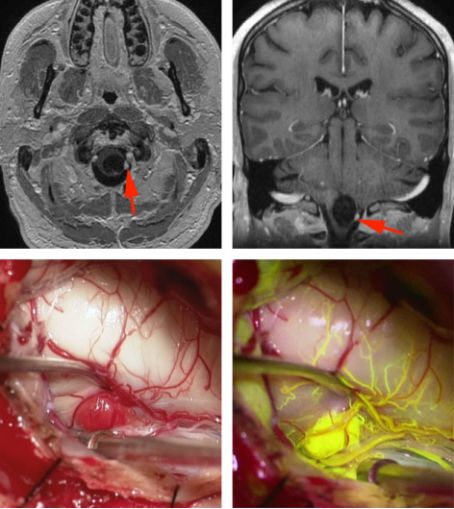

图3. 囊腔内壁结节的暴露(与图1中的上图相对应),使用膜髓帆入路。

图4. 位于延髓的囊性HB(上图MRI图像,红箭头),通过术中血管荧光造影了解畸形团的供血动脉及引流静脉的血管结构(下图)。